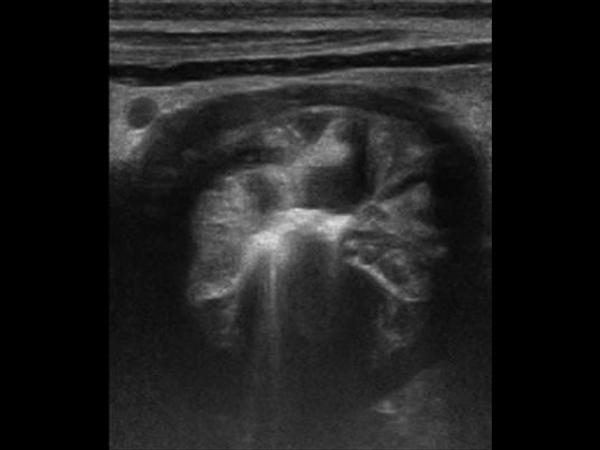

U dạ dày

» Thông tin: Nam giới – 41 tuổi.

» Lâm sàng: Đau thượng vị / Sút cân.